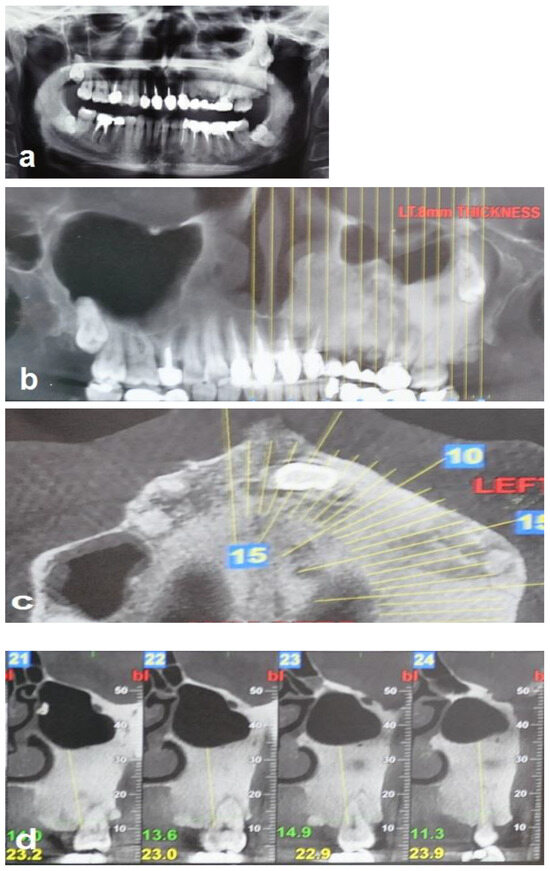

Figure 2. Radiographic views demonstrate that the FD lesion involves the left zygomaticomaxillary complex. (a,b) Panoramic radiograph and coronal CBCT show a hyperdense lesion in the left hemi-maxilla with displacement of the left maxillary sinus and the wisdom tooth, respectively. (c) Axial CBCT shows the hyperdense lesion involving the left maxilla, and (d) sagittal (cross-sectional) CBCT shows bone sclerosis and the displacement of the left maxillary sinus.

A 35-year-old woman was referred to the maxillofacial department for tooth extractions and dental implant placement in her left posterior maxillary segment. The referral was due to a suspected unidentified bone lesion in this region observed by her dental practitioner. She was an otherwise healthy patient. On examination, mild facial asymmetry was observed in her left malar area with mild expansion, without any neurological or cosmetic complaints (Figure 1). Intraoral examination revealed mild expansion of the vestibular left posterior maxillary ridge. An old fixed bridge extending from the left incisor to the first molar restored a missing canine, and first and second premolars. The first molar registered pain on percussion. Radiographic evaluation revealed a hyperdense “ground glass appearance” and sclerotic bone lesion affecting the left maxilla, left malar bone, and inferior and lateral orbital rims of the same side (Figure 2a–d).